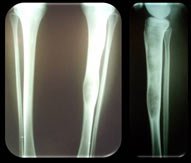

сучасна профілактична методика лікування фіброзної дисплазії великогомілкової кістки